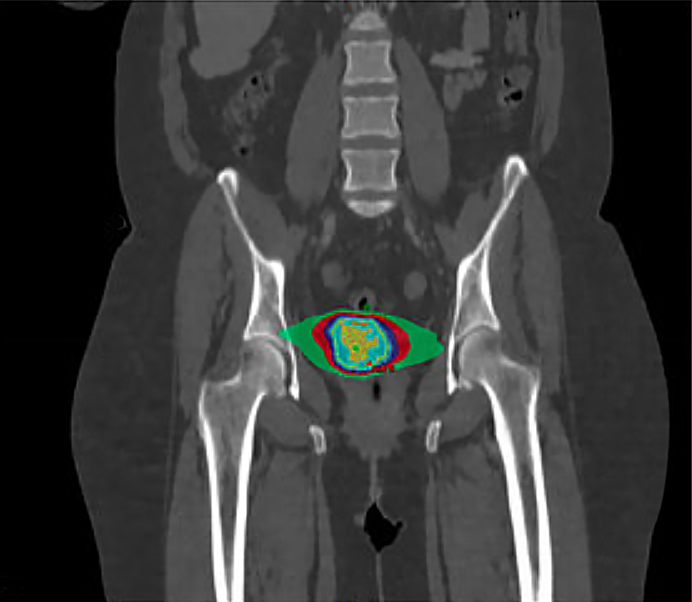

EBRT is the most common form of radiation therapy for cervical cancer. From outside the body, a machine directs an external beam precisely at the cancerous area, which may be given in daily treatments over several weeks. The goal of radiation therapy is to target the tumor while sparing as much of the healthy surrounding tissue as possible. Advanced techniques, such as image-guided and intensity-modulated radiation therapy (IG/IMRT), allow for more precise targeting and reduced side effects.

Brachytherapy involves placing a radioactive source (or sources) directly inside or near the tumor. For cervical cancer, brachytherapy is often used in conjunction with EBRT. It allows for a high dose of radiation to be delivered directly to the cervix while minimizing exposure to surrounding tissue and structures. Brachytherapy can be delivered as low-dose rate (LDR) or high-dose rate (HDR) therapy, which gives the radiation oncologist more options in how to treat the cancer. HDR is more commonly used in cervical cancer due to its convenience and effectiveness, delivering a productive dose of radiations in fewer sessions.